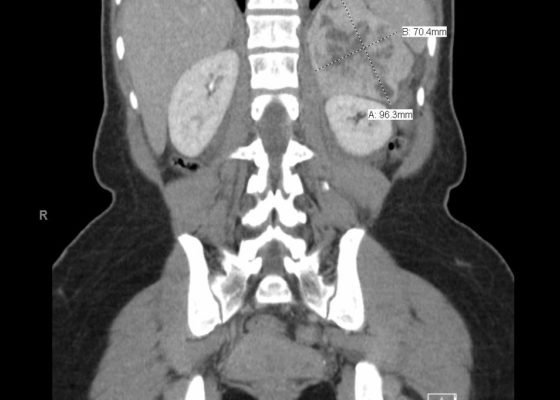

DOI: https://doi.org/10.21980/J8KW63ED work-up: BMP within normal limits (WNL), white blood cell (WBC) 27.4, ECG showed sinus tachycardia, nonspecific ST segment abnormalities, BNP and troponin were within normal limits, HR 146 beats/minute, CT abdomen/pelvis showed a 10-cm-heterogenous enhancing left adrenal mass (anterior-posterior view [shown in red], lateral view [shown in blue]).